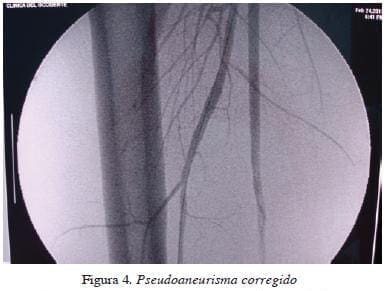

Durante un periodo de dos años se trataron por vía endovascular siete pacientes con trauma vascular periférico, así: uno con seudoaneurisma y fístula carotídea yugular; dos con fístulas arterio-venosas en la región femoro-poplítea; una paciente con laceración de la segunda porción de la arteria subclavia izquierda por herida por arma de fuego con presencia de shock; uno con un seudoaneurisma roto del tercio proximal de la arteria tibial anterior (figuras 1 y 2); uno con trauma pélvico cerrado con sangrado secundario a lesión de la arteria ilio-lumbar izquierda, y un paciente con un seudoaneurisma de la arteria femoral profunda secundario a una herida por arma corto-punzante (figuras 3 y 4). Los pacientes se numeraron del 1 al 7.